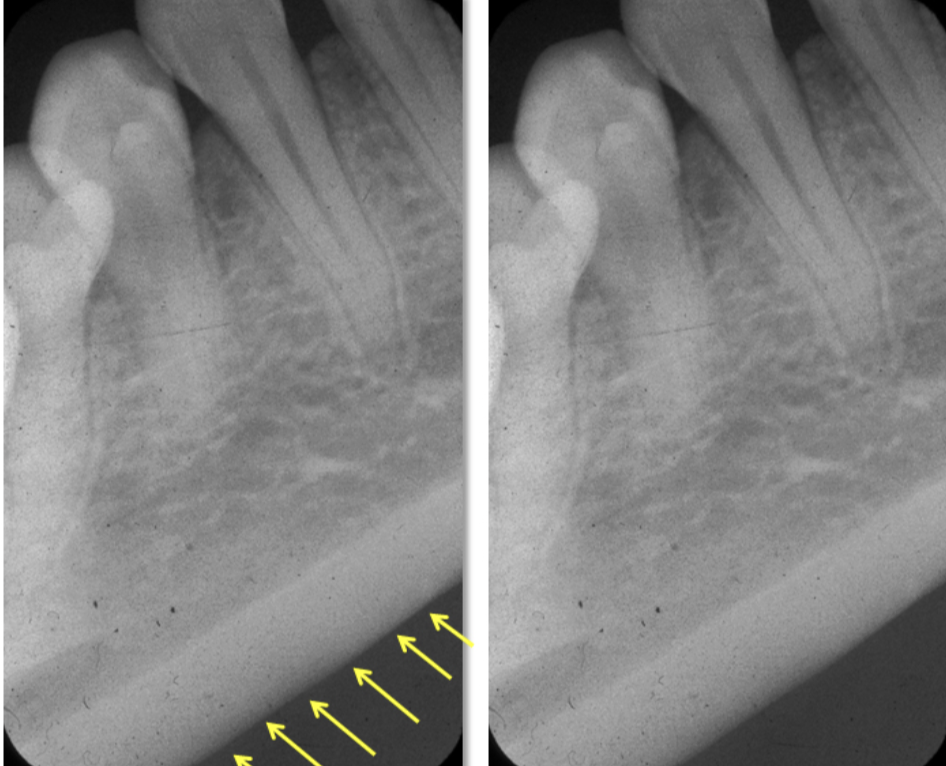

What leads to elongation in a radiograph?

When there is insufficient angulation when taking a maxillary or mandibular photo.

It means we have an excessive angulation which shortens the roots and elongates the crown.

Foreshortening= excessive vertical angulation

Elongation= insufficient vertical angulation